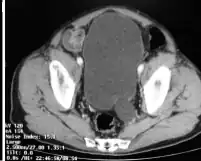

| CT-megaureter close to the bladder | |